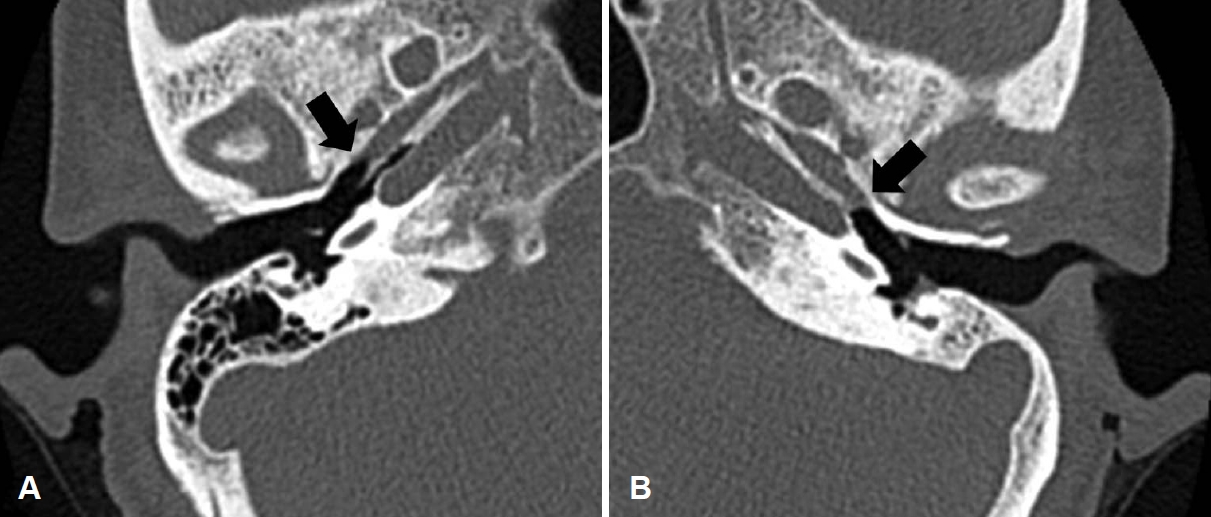

A 59-year-old female patient, without underlying diseases, presented to our clinic with a history of intermittent otorrhea persisting for approximately 20 years. The right ear exhibited normal characteristics, while the left ear displayed a medium tympanic membrane perforation with no ongoing otorrhea at the time of consultation (Fig. 1A). Pure-tone audiometry indicated a hearing threshold of 8 dB for air conduction (8 dB for bone conduction) in the right ear and 38 dB in the left ear (13 dB for bone conduction), indicative of conductive hearing loss (Fig. 1B). During an evaluation of the left ET function using the Valsalva maneuver, no sound indicative of normal tube opening was detected through the Toynbee tube. Following 1 month of confirmed absence of otorrhea recurrence, temporal bone CT imaging was conducted. The left mastoid cavity exhibited sclerotic changes, with soft-tissue density, presumed to be mucosal edema, observed in the bony portion of the ET (Fig. 2). Given the absence of otorrhea or mastoid sclerosis recurrence, endoscopic tympanoplasty without mastoidectomy was scheduled.

Fungal balls occurring commonly in the maxillary sinus typically display calcification on CT scans in approximately 80% of the cases [7]. Intralesional hyperdensity on CT indicates the presence of metal metabolites from the fungal organism [8]. In paranasal sinus fungus balls, Aspergillus, the predominant organism, utilizes its intracellular vacuole storage system to maintain zinc ion homeostasis, crucial for survival [9]. Notably, in reported cases of fungal balls in the middle ear and mastoid, calcification was not observed on CT scans [3-5]. This absence is likely due to the small size of zinc and calcium deposits, which are beyond the detection limit of conventional CT resolution [8]. While MRI could provide additional preoperative information, considering its resolution, cost, the non-invasive nature of the fungal ball, and the rarity of its localized occurrence in the ET, it may not be particularly useful [10]. Therefore, when soft tissue density is detected in the ET, it is essential to recognize that it may not signify typical mucosal edema and should be verified during surgery.

Another notable observation in this case was the localization of the fungal ball in the bony portion of the ET, a region often overlooked due to limited visibility during medial underlay tympanoplasty. To confirm the abnormal soft tissue density observed in the preoperative CT scan of the ET, the author planned lateral underlay endoscopic tympanoplasty [6]. Anatomically, as the bony portion of the ET resides in the anterosuperior quadrant, optimal visualization is achieved when a 30-degree endoscope is inserted anterior to the malleus [11]. For ET visualization, employing endoscopes with varying angles proves more advantageous than using a microscope [12]. In cases of anterior perforation, visualizing the bony portion of the ET through it is possible, but simultaneous entry of the endoscope and surgical instruments may pose challenges. Therefore, detaching the tympanic membrane from the malleus can facilitate a wider range of motion for surgical instruments.

To our knowledge, this is the first report of a fungal ball within the bony segment of an ET. When encountering soft tissue density within the bony segment of the ET on preoperative CT, it may be misconstrued as mucosal edema; nonetheless, it is imperative not to disregard this observation. Utilizing a 30-degree endoscope can facilitate achieving a lucid view of the ET.